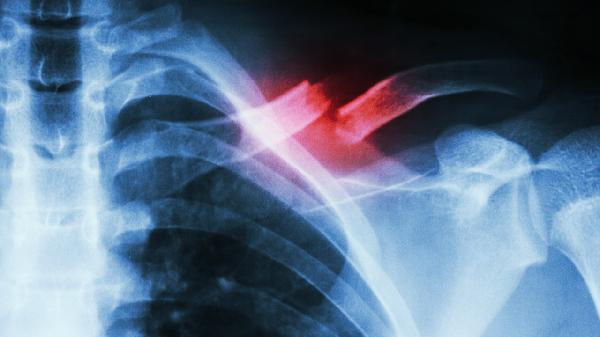

骨腫瘤包括原發(fā)性骨腫瘤和轉(zhuǎn)移性骨腫瘤,可能導(dǎo)致骨質(zhì)破壞和病理性骨折。骨腫瘤可能與基因突變、放射線暴露、其他部位腫瘤轉(zhuǎn)移等因素有關(guān)?;颊呖赡艹霈F(xiàn)局部疼痛、腫脹、病理性骨折等癥狀。治療骨腫瘤可使用唑來膦酸注射液、帕米膦酸二鈉注射液等藥物,必要時(shí)需進(jìn)行腫瘤切除或骨水泥填充手術(shù)。